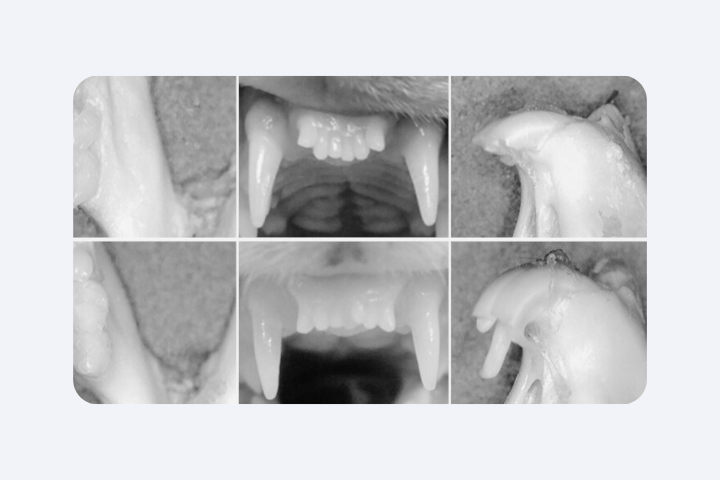

В лаборатории уже получали передние зубы с тремя корнями (так быть не должно), зубы без каналов (где тогда нервы?) или корни, растущие в сторону. Всё это — следствие нестабильного морфогенеза, которым мы пока не научились управлять в живом организме.